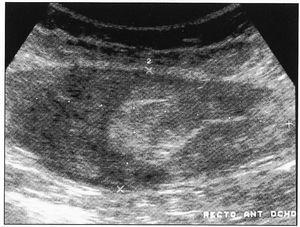

El estudio necrópsico evidenció la presencia de nódulos pulmonares bilaterales, blanquecinos, con un área central de necrosis. El hígado presentaba una superficie granulosa. A nivel abdominal, se objetivó equimosis periumbilical, en el flanco derecho y cadera izquierda, con hematomas en ambos rectos abdominales anteriores. Microscópicamente se evidenciaba un infiltrado polimorfo de linfocitos de tamaño intermedio y grandes, con nucleolos evidentes, junto a inmunoblastos a nivel de pulmón (figura 2), hígado, ganglios linfáticos e injerto renal. Existía también una importante infiltración linfocitaria a nivel de la pared de los vasos del músculo recto anterior abdominal (figura 3). El estudio inmuno-histoquímico fue positivo para ALC y CD20. Se objetivó VEB en replicación en el estudio con PCR sobre DNA obtenido del tejido afectado. La causa de muerte se atribuyó a PTLD en relación a una infección activa por VEB.

Figura 2. Infiltrado pulmonar